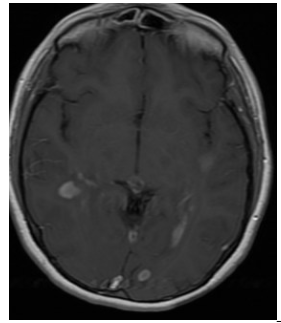

On July 17th, I went in for my 3 hour MRI (you read that right). These MRIs are brutal. I dread them every single time. This was the first time I was offered music and a break halfway thru, which helped a ton! After the MRI came the waiting game. I’ll spare you the details, but after a mix up with the radiologist, followed by him going on a two week vacation, I FINALLY received my results on August 4th. Not only were things stable, but significantly improved!! Below is a pic showing how much smaller my lesions were after only 6 months!